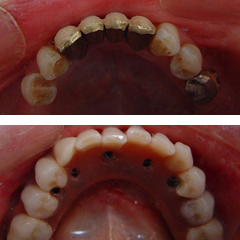

Δείτε επίσης παρακάτω σε φωτογραφίες τα στάδια της τεχνικής καθώς και περιστατικά άμεσης φόρτισης που έχουν θεραπευτεί στο ιατρείο μας σε μια μέρα.

Στάδιο 1:Εξέταση-ενημέρωση, Στάδιο 2:Τοποθέτηση των εμφυτευμάτων

Στάδιο 3:Καταγραφή των σχέσεων των γνάθων,

Στάδιο 4:Αναμονή

Στάδιο 5:Παράδοση εργασίας,

Στάδιο 6:Καινούργια δόντια σε μια μέρα